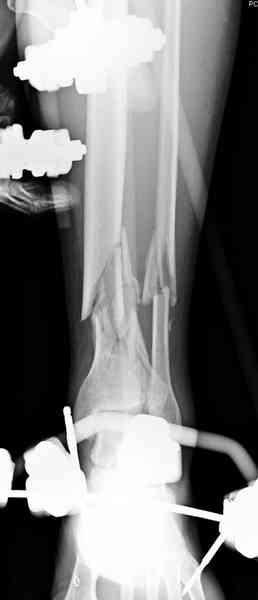

При высокоскоростных переломах редко можно встретить изолированную травму пилона, и в моей практике изолированные травмы большая редкость, поэтому, как дополнение к обсуждаемой теме, решил представить свежий, двухдневной давности случай.

Предыдущей сменой до 4:00 утра по поводу открытого перелома бедра, тибиал плато, пилон и надколенника сделана операция.

Пострадавшему 21 г., травма скоростная, после I&D с расширением раны, на бедре сделана операция ретроградным интрамедуллярным штифтом, остеосинтез с частичной резекцией надколенника и ушивание собственной связки.

В настоящее время больной в реанимации по поводу Черепно Мозговой Травмы и состояние улучшается. Запланировал ушивание раны в пятницу, если позволит состояние мягких тканей и при отсутстви отека возможно удастся просунуть перкутанномедиальную пластину.

КТ пилона имеем.